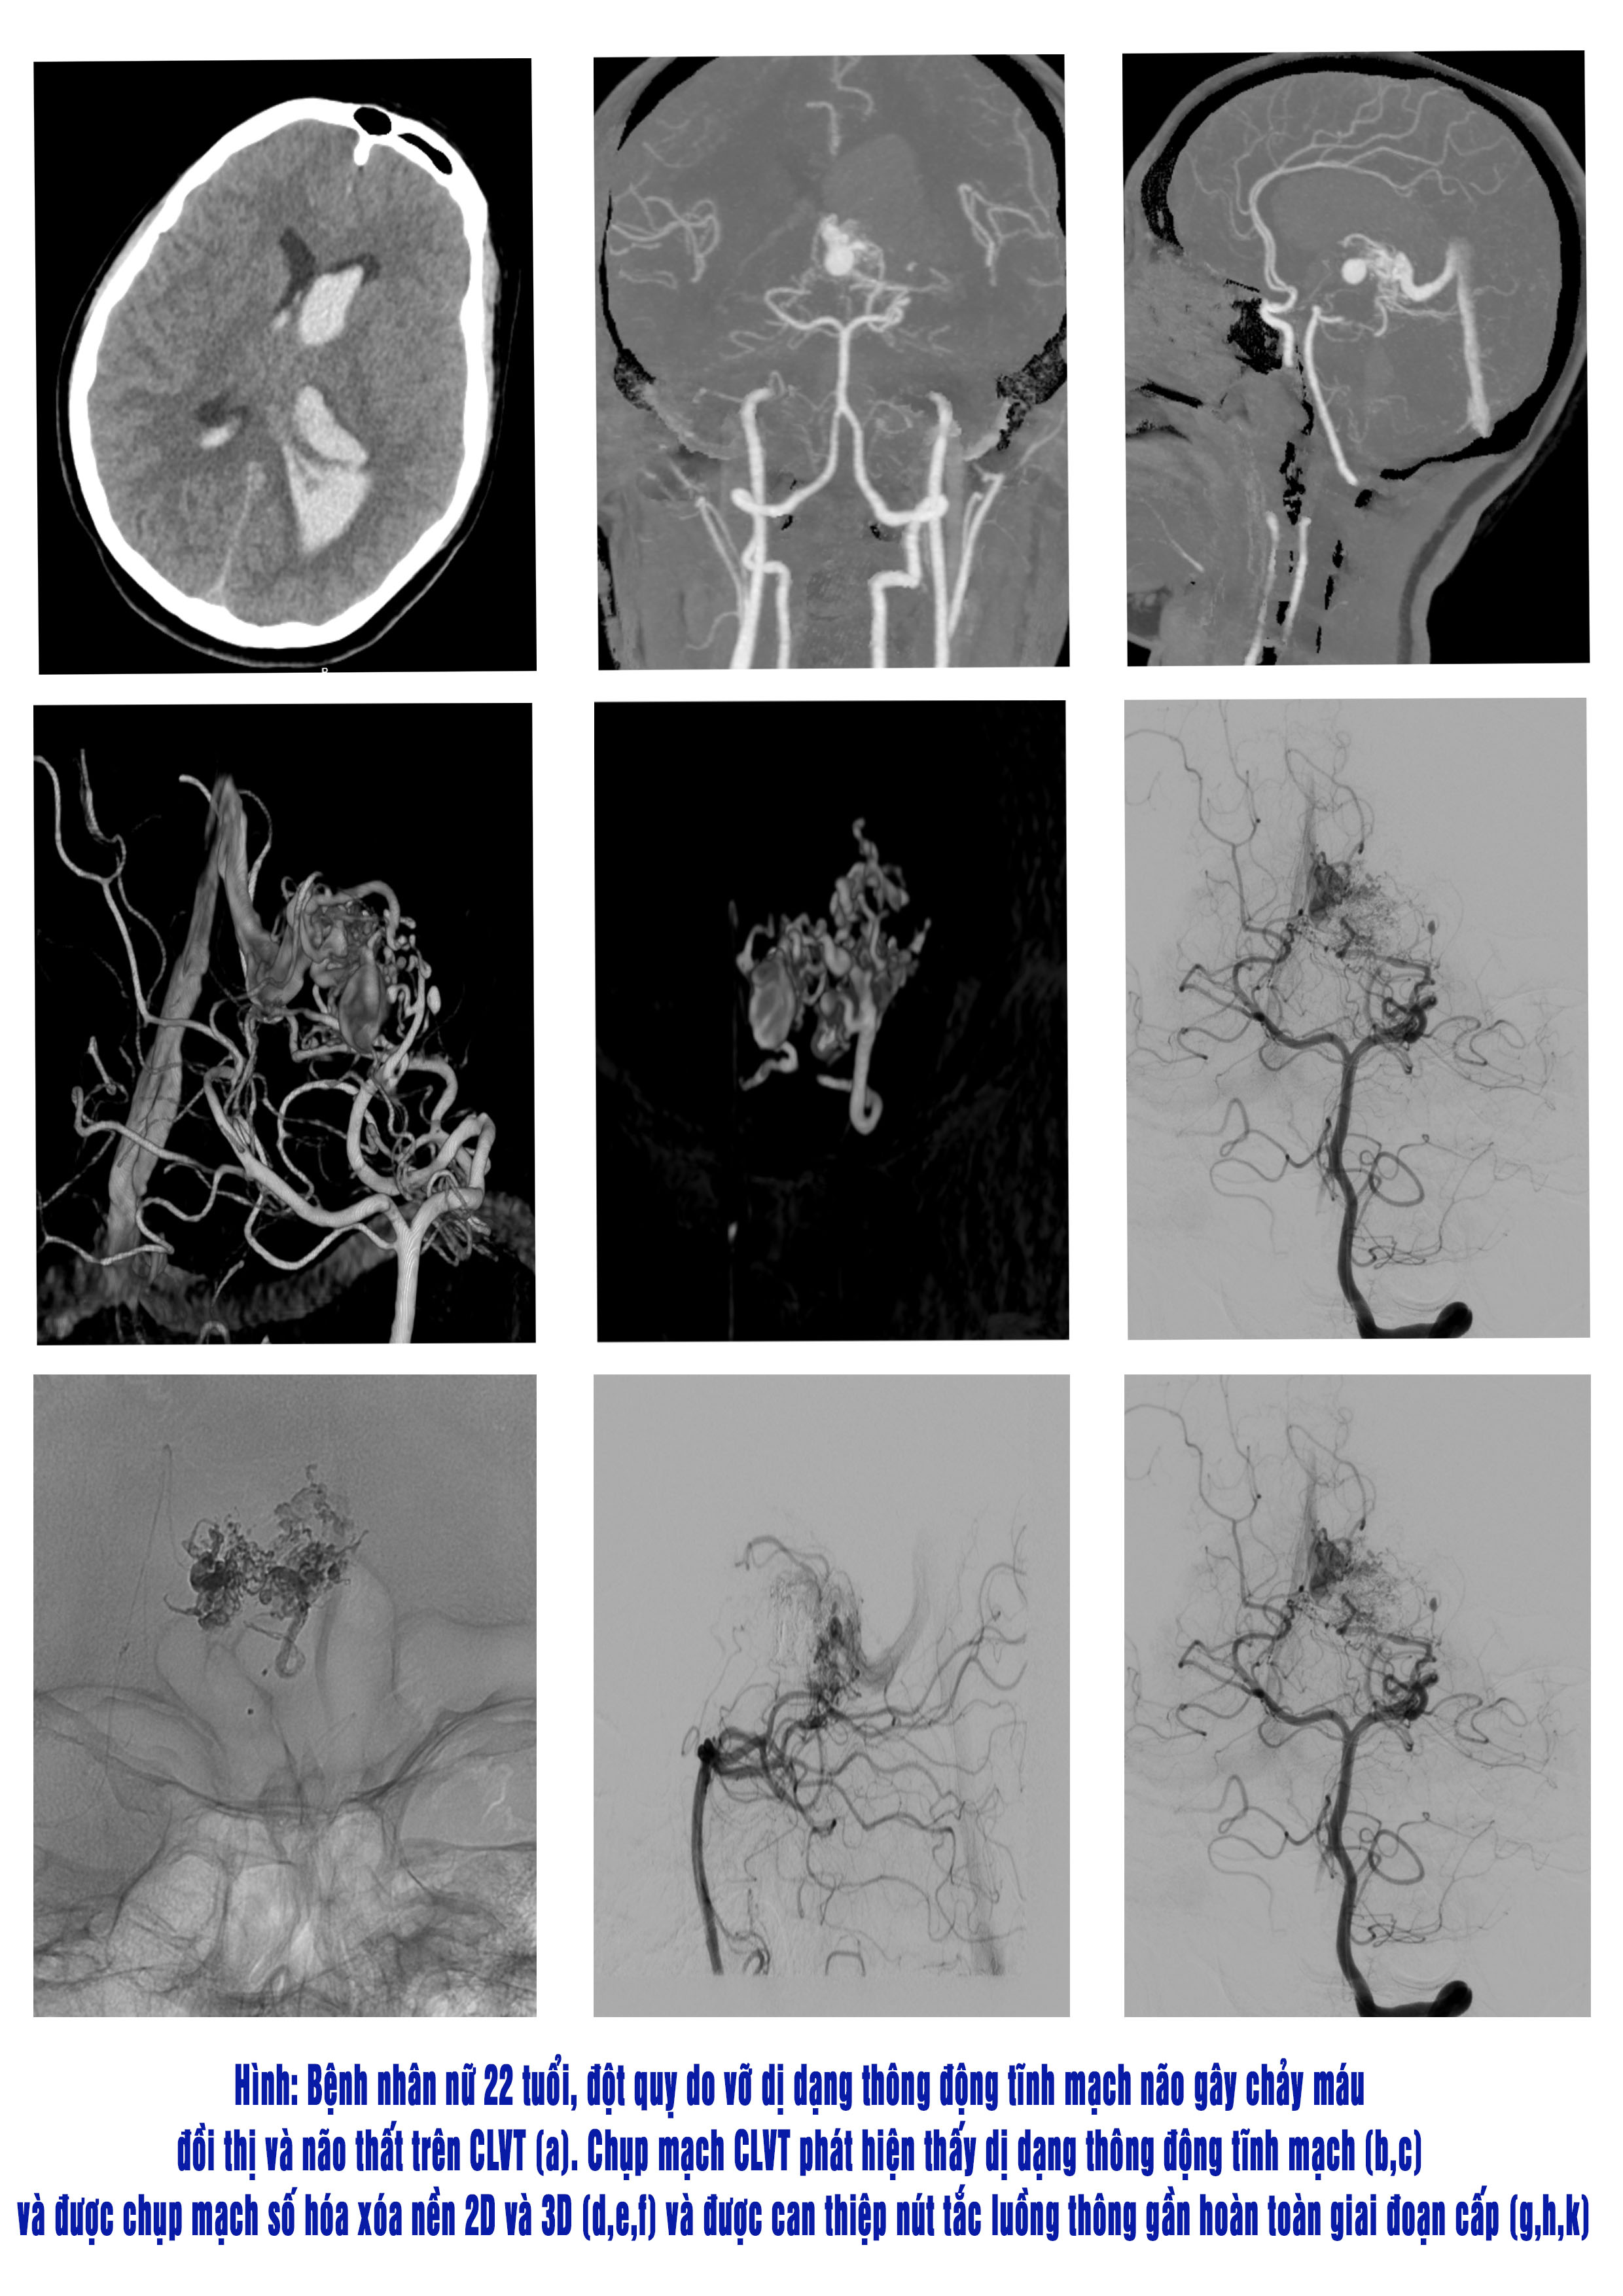

– Thứ hai, đối với thể vỡ sẽ gây chảy máu tạo khối máu tụ trong não, não thất hoặc màng não. Nguy cơ vỡ dị dạng thông động tĩnh mạch phụ thuộc vị trí, kích thước và cấu trúc ổ dị dạng.

• Chụp cắt lớp vi tính cho phép chẩn đoán vị trí khối máu tụ, ổ dị dạng.

• Chụp mạch não cắt lớp vi tính xác định được ổ dị dạng thông động tĩnh mạch, đánh giá hình thái và cấu trúc ổ dị dạng, qua đó sơ bộ định hướng điều trị.

• Chụp mạch não số hoá xoá nền là tiêu chuẩn vàng xác định chẩn đoán và quyết định lựa chọn phương pháp điều trị.

• Điều trị can thiệp nội mạch nút tắc ổ dị dạng bằng Onyx có kết quả tắc tốt hơn và an toàn hơn so với dùng loại keo Histoacryl. (Hình 6)